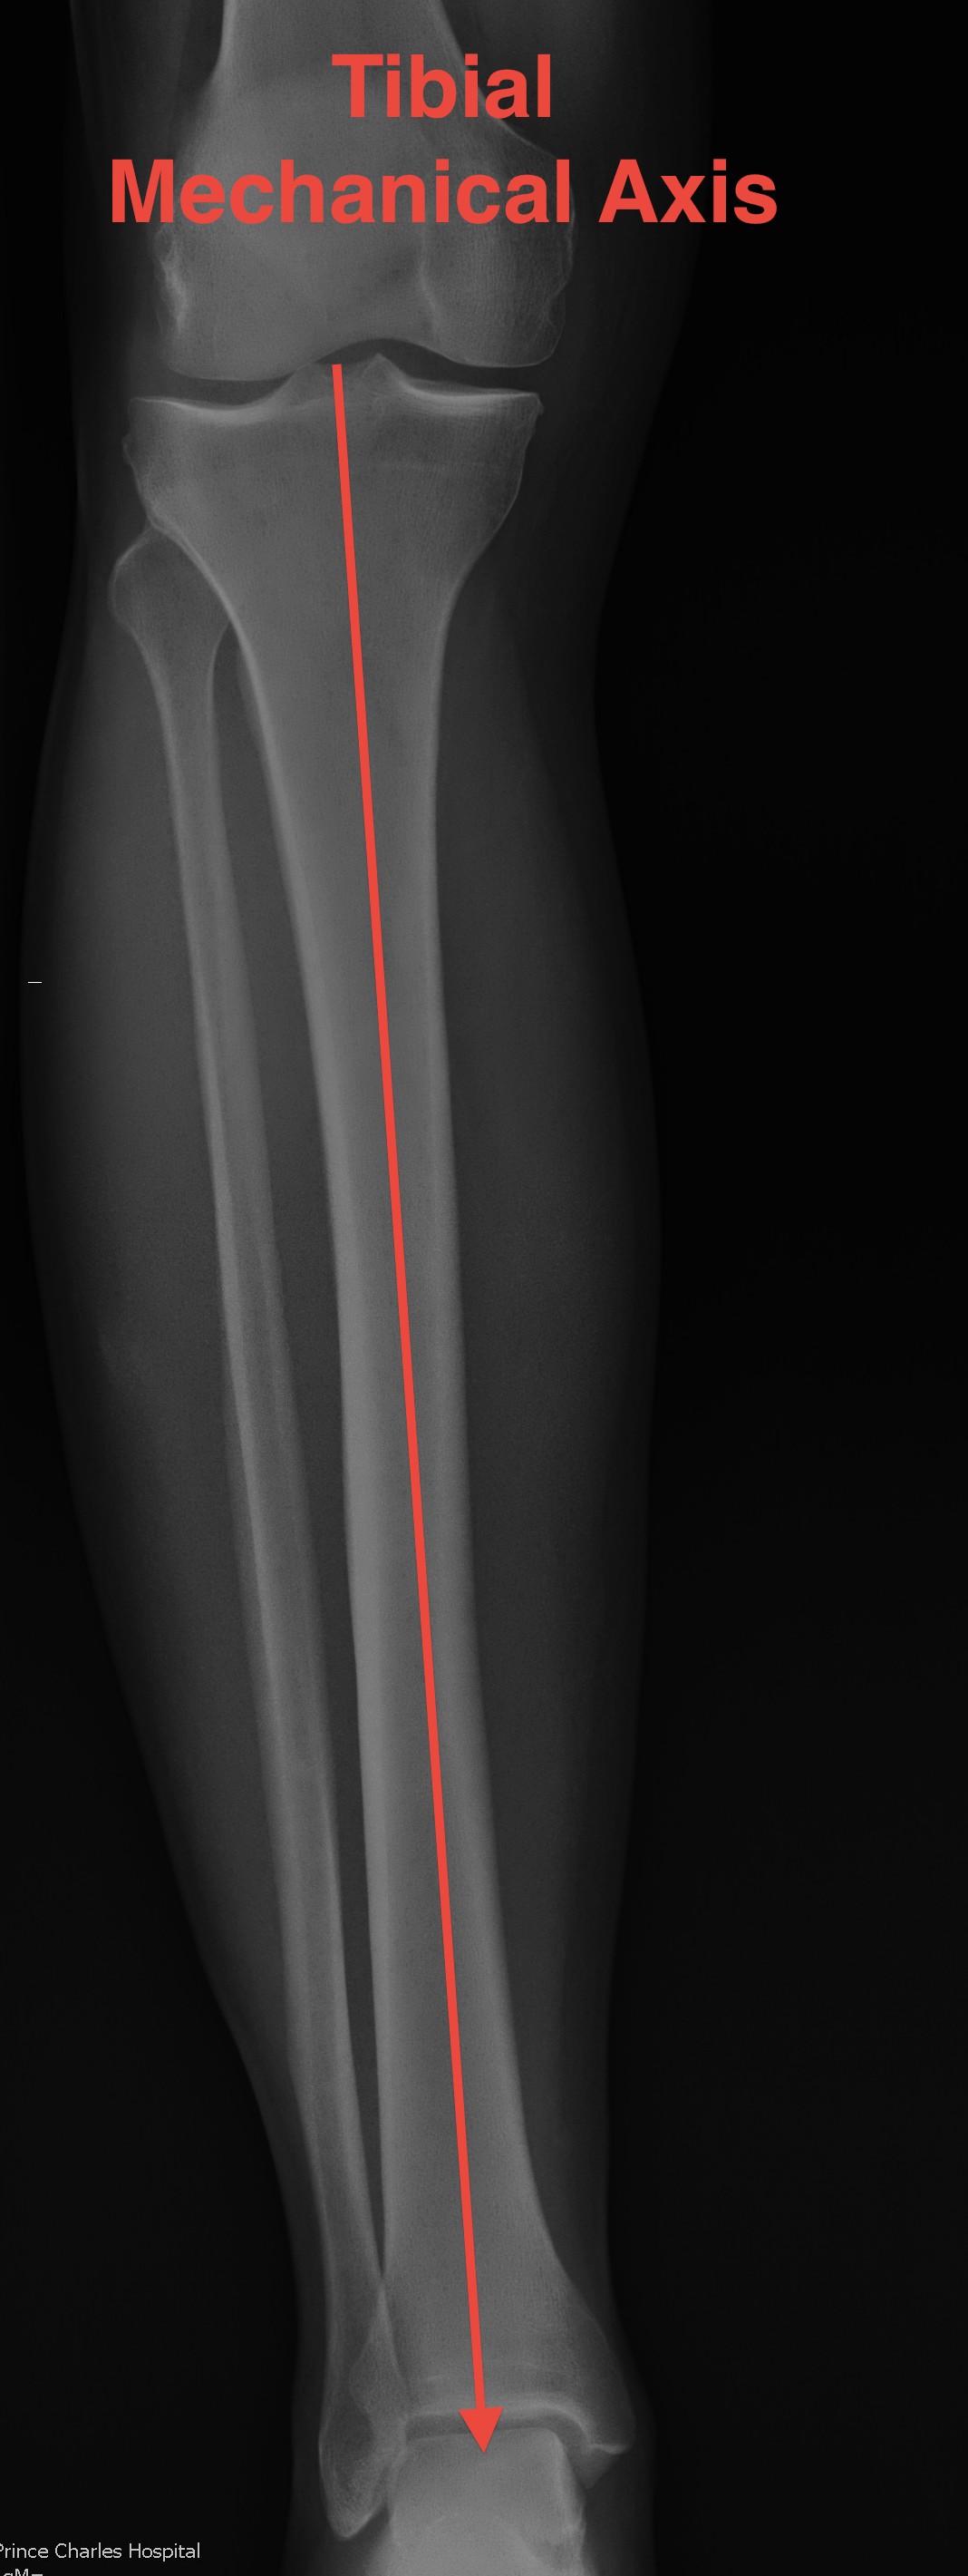

Mechanical Axis Tibial (MAT)

- centre of tibial spines to centre of weight bearing axis of the distal tibia

- usually same as AAT

- except with traumatic or congenital bowing